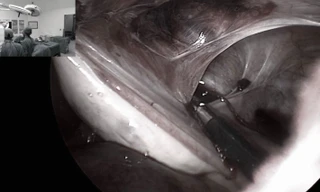

TPO - Nhập viện trong tình trạng đau bụng dữ dội, nữ bệnh nhân được bác sĩ chẩn đoán bị dính buồng trứng và vòi trứng vào thành bụng. Trước đó, bệnh nhân đã 2 lần vượt cạn bằng phương pháp mổ bắt con.

TPO - Với kỹ thuật mới này, bệnh nhi sẽ được ra viện ngay ngày hôm sau và vết sẹo phẫu thuật nội soi có tính thảm mỹ cao với chỉ đường rạch 2mm, sau mổ hầu như không nhìn thấy sẹo và đặc biệt là không làm ảnh hưởng đến chức năng sinh sản của trẻ…